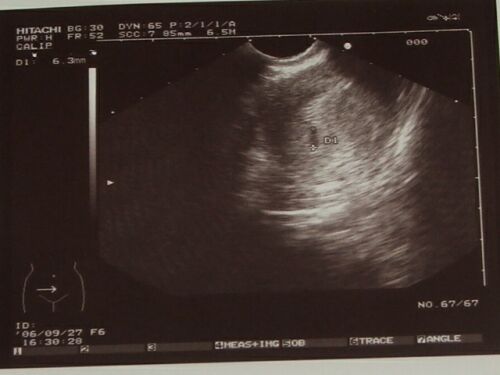

Itt a tegnapi UH kép, hogy lássátok, tényleg nagyon mini még. 2006.09.28 19:53

Én 10. 10-én megyek uh-ra, akkor majd kiderül, hogy mekkora az akkora!